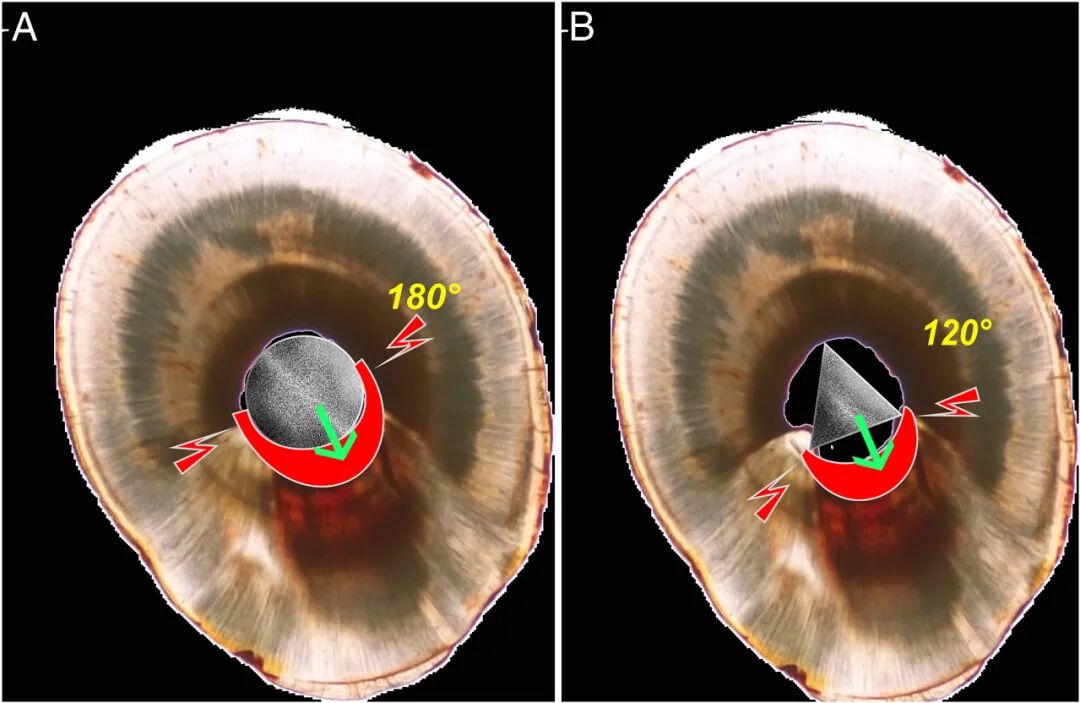

牙本质的去除量因分离器械的截面而变化。如图6所示,移除圆形器械需要在器械周围形成180°角。而在三角形切面中,去除的牙本质组织的量要更少。此外,在这些根管中,根管贯穿或带状穿孔的风险肯定会增加;因此,这一操作需小心谨慎。

图6. (A) 如果器械截面为圆形,则需要在分离的器械周围形成一个圆周>180° 的空间,以便松解断针。(B) 如果是三角形截面,断针周围120° 范围的牙本质去除就足够了。